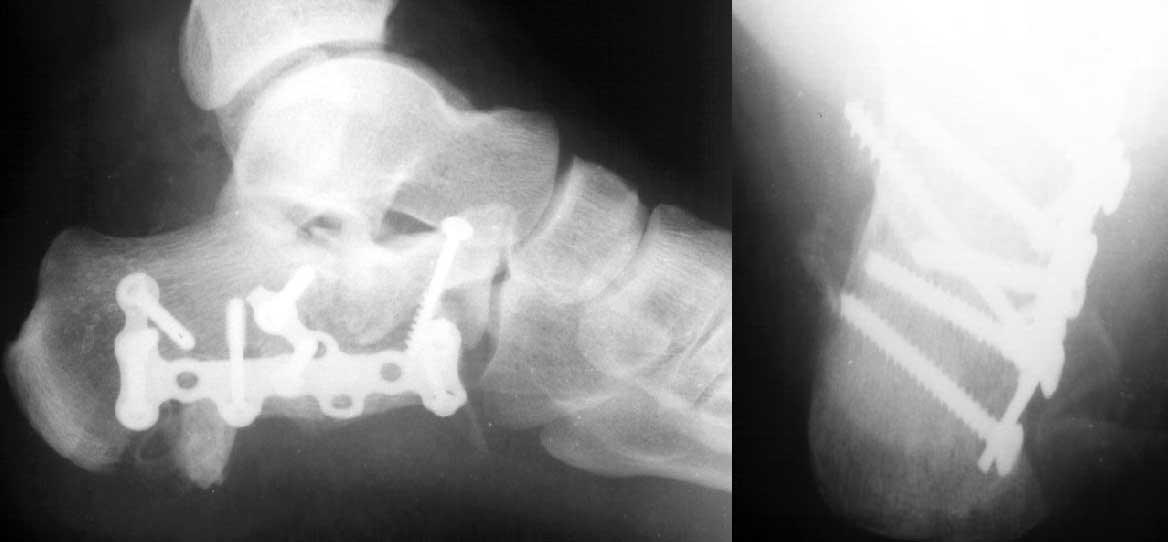

Пациент 36 лет поступил к нам с травмой стоп после падени яс высоты 6 м. С одной стороны подвывих в суставе Лисфранка, с другой переломпяточной кости (см. приложение).

У нас при обсуждении мнения разошлись. Каков тут оптимальный план лечения? Если оперировать,удастся ли закрыто достичь восстановления конгруэнтности таранно-пяточного сустава? Удастся ли зафиксировать результат открытого вправления стандартной пяточной фигурной пластиной, или лучше фиксировать отдельными треть-трубчатыми пластинами?Заранее спасибо.

Данный перелом можно классифицировать как "языкообразный" (по Essex-Lopresti), но имеется еще раздробление переднего отдела пяточной кости.

Как метод выбора, по мнению нашей клиники, является закрытая аксиальная репозиция аксиальная фиксация "языкообразного" фрагмента винтом Шанца под контролем ЭОПа. Технически это возможно в сроки до 10 дней, важно правильно

выбрать изначальную точку введения винта, стремясь винт ввести максимально перпендикулярно по отношению к верхнему краю языкообразного фрагмента, выполнить тракцию по длине и низведение.